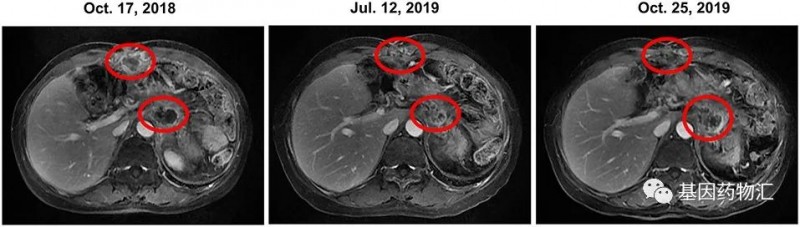

2018年9月~2019年1月,患者接受了6个周期的伊立替康治疗,但CA19-9上升;2018年10月~2019年11月,患者使用奥拉帕利+伊立替康治疗,病情一直稳定,最后因CA19-9升高而更换方案;2019年11月,患者开始接受SOX化疗,但疾病仍然进展。

从2019年12月,患者开始接受曲美替尼(2 mg,每日一次)+羟氯喹(Hydroxychloroquine,200 mg,每日两次)方案治疗。治疗的第一个月,患者的CA19-9水平继续上升,于是将羟氯喹的剂量提升至400 mg、每天两次。此后的6个月,患者疾病一直保持稳定。